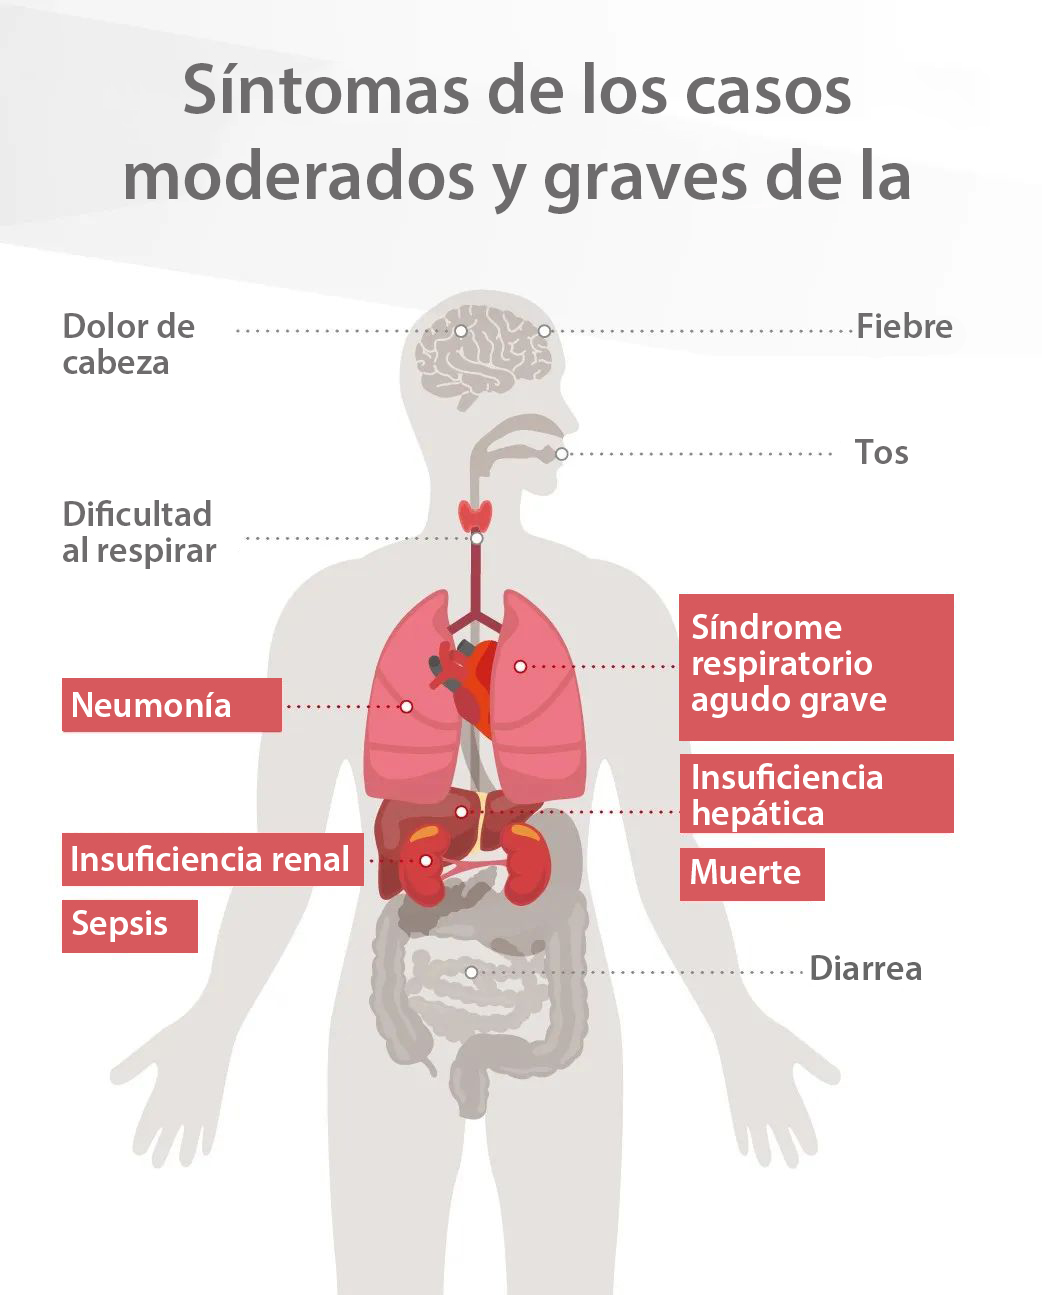

Aunque la mayorÃa de los casos de coronavirus confirmados son moderados, los pacientes mÃḂs graves pueden sufrir un rÃḂpido deterioro que genere insuficiencias respiratorias, choques sépticos o fallos orgÃḂnicos mÃẃltiples que pongan en riesgo su vida. Los dirigentes de la OMS estiman que la tasa de mortalidad mundial por los casos de la COVID-19 se sitÃẃa entorno al?3.4%. [1] La identificaciÃġn temprana de los indicadores que distinguen a los pacientes graves de los moderados puede ayudar a acelerar las intervenciones médicas, como trasladar casos crÃticos a la UCI, y reducir asà la tasa de mortalidad y optimizar el uso de los recursos médicos tan sumamente extenuados.